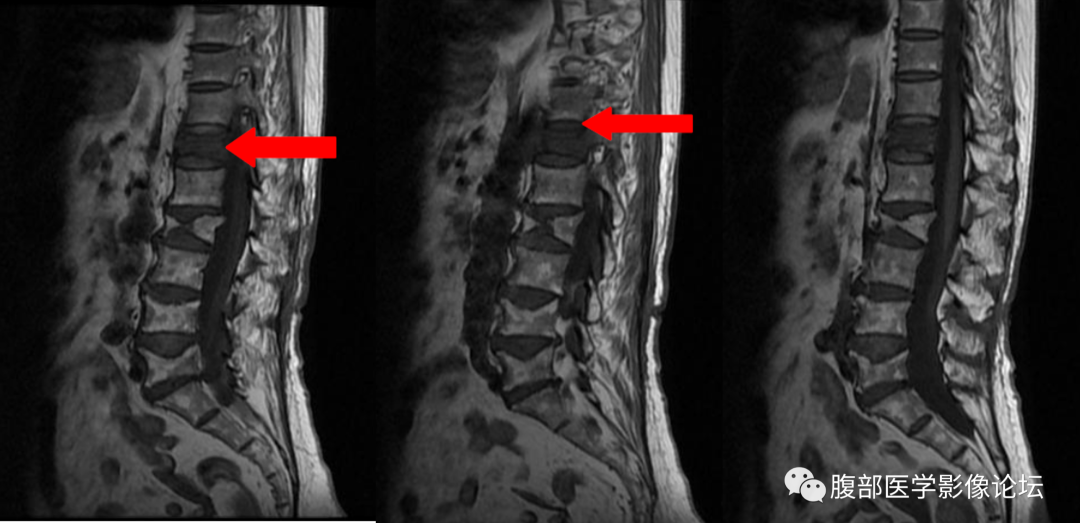

本院一例病例,患者,女,76 岁,因胸背疼痛来院行核磁检查,诊断压缩性骨折,行骨水泥手术,疼痛缓解,十天后,胸背疼痛加重,转院至省城南昌,行穿刺活检,病理提示转移性腺癌。

发生误诊,只是片面的看到了椎体在抑脂像呈高信号,而没有从细节方面着手。

1、T1WI 椎体内脂肪残留程度

良性骨折:椎体内至少残留部分脂肪成分(正常黄骨髓部分残留) 恶性骨折:椎体内黄骨髓被肿瘤组织完全取代,椎体脂肪信号完全消失。

2、椎体后柱有无受累

良性骨折:一般不累及椎弓根、椎板等后柱结构 恶性骨折:常累及椎弓根、椎板等后柱结构

椎体良性与恶性骨折的鉴别其实还有一些鉴别点,但是笔者认为上面六点是最主要的,同时需要指出,任何单独一个鉴别点都不是绝对的,就拿本例来说,仔细看,T1WI 系列还是可以看到一小部分黄骨髓的,但是椎弓根有受累,又是老年人,我们要想到转移瘤的可能,所以我们要仔细阅片,避免不必要的医疗纠纷。